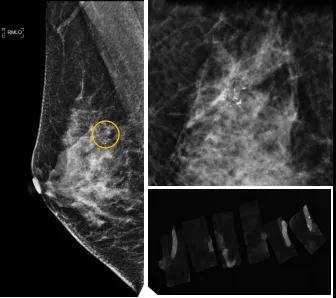

小到1—2mm的鈣化也能活檢!西安國際醫(yī)學(xué)中心醫(yī)院采用精準(zhǔn)技術(shù)讓乳腺早癌無處可逃

46歲的某女士在西安國際醫(yī)學(xué)中心醫(yī)院體檢時(shí),行乳腺X線攝影(俗稱鉬靶)發(fā)現(xiàn)右乳可疑簇狀鈣化,分布范圍不到1厘米,臨床觸不到,超聲很難發(fā)現(xiàn),但是這種鈣化風(fēng)險(xiǎn)比較高,依據(jù)國際BI-RADS指南需要明確病理!

西安國際醫(yī)學(xué)中心醫(yī)院影像診療中心陳寶瑩副主任帶領(lǐng)的團(tuán)隊(duì),采用全數(shù)字化乳腺X線三維立體定位系統(tǒng)可實(shí)施。這個(gè)團(tuán)隊(duì)的成員大部分來自知名三甲醫(yī)院,有著十余年影像引導(dǎo)下乳腺介入診療的經(jīng)驗(yàn),X線引導(dǎo)穿刺定位和活檢例數(shù)居西北前列。為減少患者創(chuàng)傷,在詳細(xì)判讀了患者資料,并與患者及甲乳外科劉曉敏主任充分溝通的基礎(chǔ)上,團(tuán)隊(duì)確定采用全數(shù)字化乳腺X線三維立體定位系統(tǒng)下實(shí)施粗針活檢。

當(dāng)天,乳腺X線三維立體定位系統(tǒng)清晰顯示出了所有鈣化。為了獲取充足的組織量,保證病理診斷的準(zhǔn)確性,團(tuán)隊(duì)選用14G穿刺針并多點(diǎn)、多角度取材,組織取出后,又立即在高清標(biāo)本攝影系統(tǒng)中進(jìn)行投照,從而確定了取出組織中具有足夠的可疑鈣化。整個(gè)過程患者無任何不適,活檢結(jié)束后即回家觀察。

后期病理回報(bào)活檢組織條中均查見導(dǎo)管原位癌。該女士及家屬對西安國際醫(yī)學(xué)中心醫(yī)院早期發(fā)現(xiàn)并精準(zhǔn)確診病變的技術(shù)給予了高度的贊揚(yáng)。

乳腺導(dǎo)管原位癌屬于早期的腫瘤性導(dǎo)管內(nèi)病變,有發(fā)展為浸潤性癌的傾向,需要早發(fā)現(xiàn)早治療,其預(yù)后明顯優(yōu)于浸潤性癌。2020年癌癥雜志的文章指出,近90%的導(dǎo)管原位癌僅表現(xiàn)為不可觸及的可疑鈣化,乳腺X線檢查是發(fā)現(xiàn)微小鈣化最敏感的方式,因此70–90%的導(dǎo)管原位癌是通過乳腺X線篩查發(fā)現(xiàn)。多年來國內(nèi)外指南,如美國國家綜合癌癥網(wǎng)絡(luò)(NCCN)指南及中國抗癌協(xié)會乳腺癌診治指南均建議40歲以上女性每年通過雙乳X線檢查(鉬靶)進(jìn)行乳腺癌篩查,高危人群建議提前進(jìn)行篩查(小于40歲)。由于雙乳X線篩查的推廣,歐美等國家導(dǎo)管原位癌的檢出率極大提高,明顯降低了乳腺癌的死亡率。在我國規(guī)范進(jìn)行乳腺X線篩查的人群比例比較低,很多人發(fā)現(xiàn)腫瘤時(shí)已經(jīng)為浸潤性癌,因此提醒大家高度重視規(guī)范的雙乳X線篩查。通過乳腺X線篩查發(fā)現(xiàn)的可疑鈣化需要在X線引導(dǎo)下精準(zhǔn)定位,進(jìn)行粗針穿刺或真空輔助旋切活檢,以獲得準(zhǔn)確的病理學(xué)結(jié)果,給予及時(shí)有效的治療。